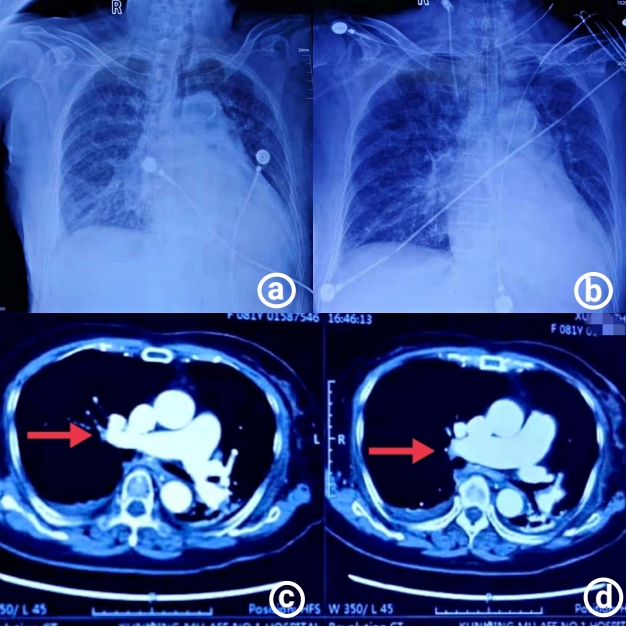

1.4 诊治经过及临床转归入院诊断:急性胃肠炎。给予“拉氧头孢2 g q12 h静脉滴注”抗感染,冠心病二级预防,控制血压,控制心室率,补液,维持电解质平衡等对症治疗,2020年12月1日19:00患者出现胸闷、喘息、呼吸困难、烦躁,血气分析:pH 7.39,PO2 78 mmHg,PCO2 19 mmHg,乳酸4.7 mmol/L,氧合指数128 mmHg,面罩给氧,氧流量10 L/min,白细胞33×109/L,中性粒细胞百分比88.50%,血红蛋白69 g/L,降钙素原6.73 ng/mL,超敏C反应蛋白 > 200 mg/L;胸片提示双肺多发渗出病灶(图 1A),给予高流量吸氧,流量50 L/min,FiO2 90%,呼吸科会诊指导对症处理。2020年12月2日肌红蛋白165.36 μ g/L,肌钙蛋白Ⅰ 19.567 ng/L,B型钠尿钛 > 4 500 pg/mL;患者肌钙蛋白Ⅰ和心衰指标明显升高,呼吸困难明显,口唇发绀,出现谵妄症状,不排除急性冠脉综合征可能,请心内科、ICU会诊后,随即转入ICU,血气分析:pH 7.15,PO2 103 mmHg,PCO2 27 mmHg,BE -17.9 mmol/L,HCO3- 11 mmol/L,乳酸8.4 mmol/L,氧合指数103 mmHg。患者氧饱和度进行性下降,呼吸骤停,立即给予气管插管呼吸机辅助呼吸,2~3 h内患者先后出现4次心搏骤停,间断心肺复苏成功后,立即复查心电图示快速房颤,T波改变,复查心肌酶学及感染相关蛋白,呼吸、心率、氧合稳定后,用转运呼吸机将患者快速转至心导管室急诊行PCI,提示:左前降支狭窄30%~40%,右冠狭窄20%~30%,排除急性心肌梗死;床旁心脏超声提示:右室、左房和升主动脉内径扩大,肺动脉收缩压增高,左室舒缩功能减弱;患者体温39℃,立即行血培养、床旁纤支镜检查取深部痰液行痰培养,同时送血、肺泡灌洗液进行病原宏基因组学检测。

| 图 1 患者影像学结果(A:患者入院胸部X线,双肺多发渗出病灶;B:治疗后胸部X线,肺部炎症渗出好转;C、D:患者胸部CTA结果,箭头所指处为右肺下叶前基底段动脉局部可疑充盈缺损影,肺栓可能) |

综合征状、体征及检验结果考虑患者为:急性胃肠道感染、脓毒性休克、多器官功能障碍综合征、急性肺栓塞可能,立即予“亚胺培南西司他丁钠1 g q6 h联合万古霉素0.5 g q12 h”抗感染,呼吸循环支持,去甲肾上腺素应用,补液,低分子肝素抗凝,同时兼顾心功能,纠正贫血,人血白蛋白、呋塞米应用,免疫球蛋白冲击20 g/d,改善免疫功能,共用5 d,保护重要脏器功能,纠正内环境紊乱等对症治疗。根据血药浓度及肝肾功能调整抗生素剂量,但患者仍有间断发热,三次血痰培养均为阴性。2020年12月5日血液宏基因组学检查报告为阴性,肺泡灌洗液宏基因组学检查报告提示“TW”,调整抗生素为头孢哌酮舒巴坦钠3 g q8 h、氟康唑400 mg qd、复方磺胺甲恶唑片2片q12 h协同抗感染治疗。2020年12月6日行胸部血管CTA检查提示:右肺下叶前基底段动脉局部可疑充盈缺损影,肺栓塞可能,继续予低分子肝素抗凝治疗(图 1C、D)。2020年12月7日床边胸片提示肺部炎症渗出好转(图 1B),但患者仍存在循环不稳定,阵发性房颤,需大剂量去甲肾上腺素维持血压,予强心(去乙酰毛地黄苷及左西孟旦)、利尿治疗,心功能改善,循环趋于稳定;经针对性抗感染治疗后患者白介素6、降钙素原、C反应蛋白指标下降,淋巴亚群免疫指标恢复正常。患者于2020年12月9日拔除气管导管,予无创呼吸机与高流量辅助通气交替应用,逐渐过渡为面罩给氧,但患者出现心率升高伴有谵妄表现,心率波动于130~150次/min,为窦性心动过速伴有频发室早,再次评估病情后,加强排痰,纠正贫血、予艾司洛尔、美托洛尔及伊伐布雷定控制心室率,左西孟旦、辅酶Q10改善心功能[3],睡前口服阿普唑仑联合奥氮平改善睡眠、抗焦虑、谵妄治疗后,病情逐渐好转。2020年12月11日复查肺泡灌洗液宏基因组学未再检测出TW;2020年12月14日复查胸部CT示双肺片状磨玻璃影及实变影较前吸收,双侧胸腔积液较前吸收,逐渐停用抗生素,更换低分子肝素为利伐沙班口服抗凝治疗。经过21 d治疗,患者于2020年12月20日治愈出院,出院时感染指标恢复正常,肝、肾功能正常,三大常规均无异常。